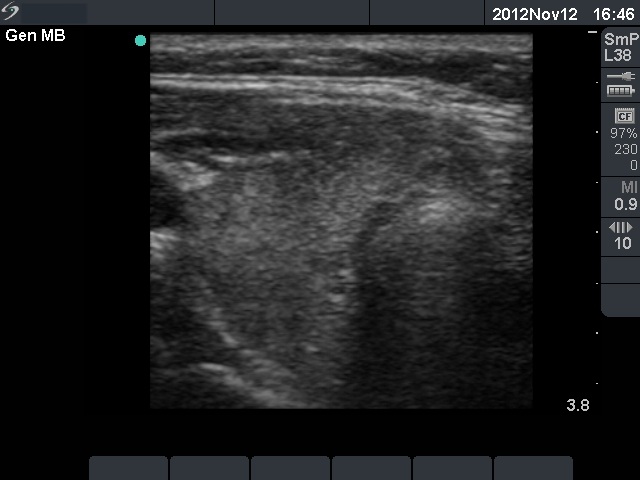

Follow-up examination 4 weeks later (3rd row of images):

He had no complaints with euthyroid hormone levels (TSH 2.41 mIU/L, FT4 14.1 pM/L) and normal CRP (1.1 mg/L) and ESR 9 mm/H.

Ultrasonography demonstrated an almost complete normalization.